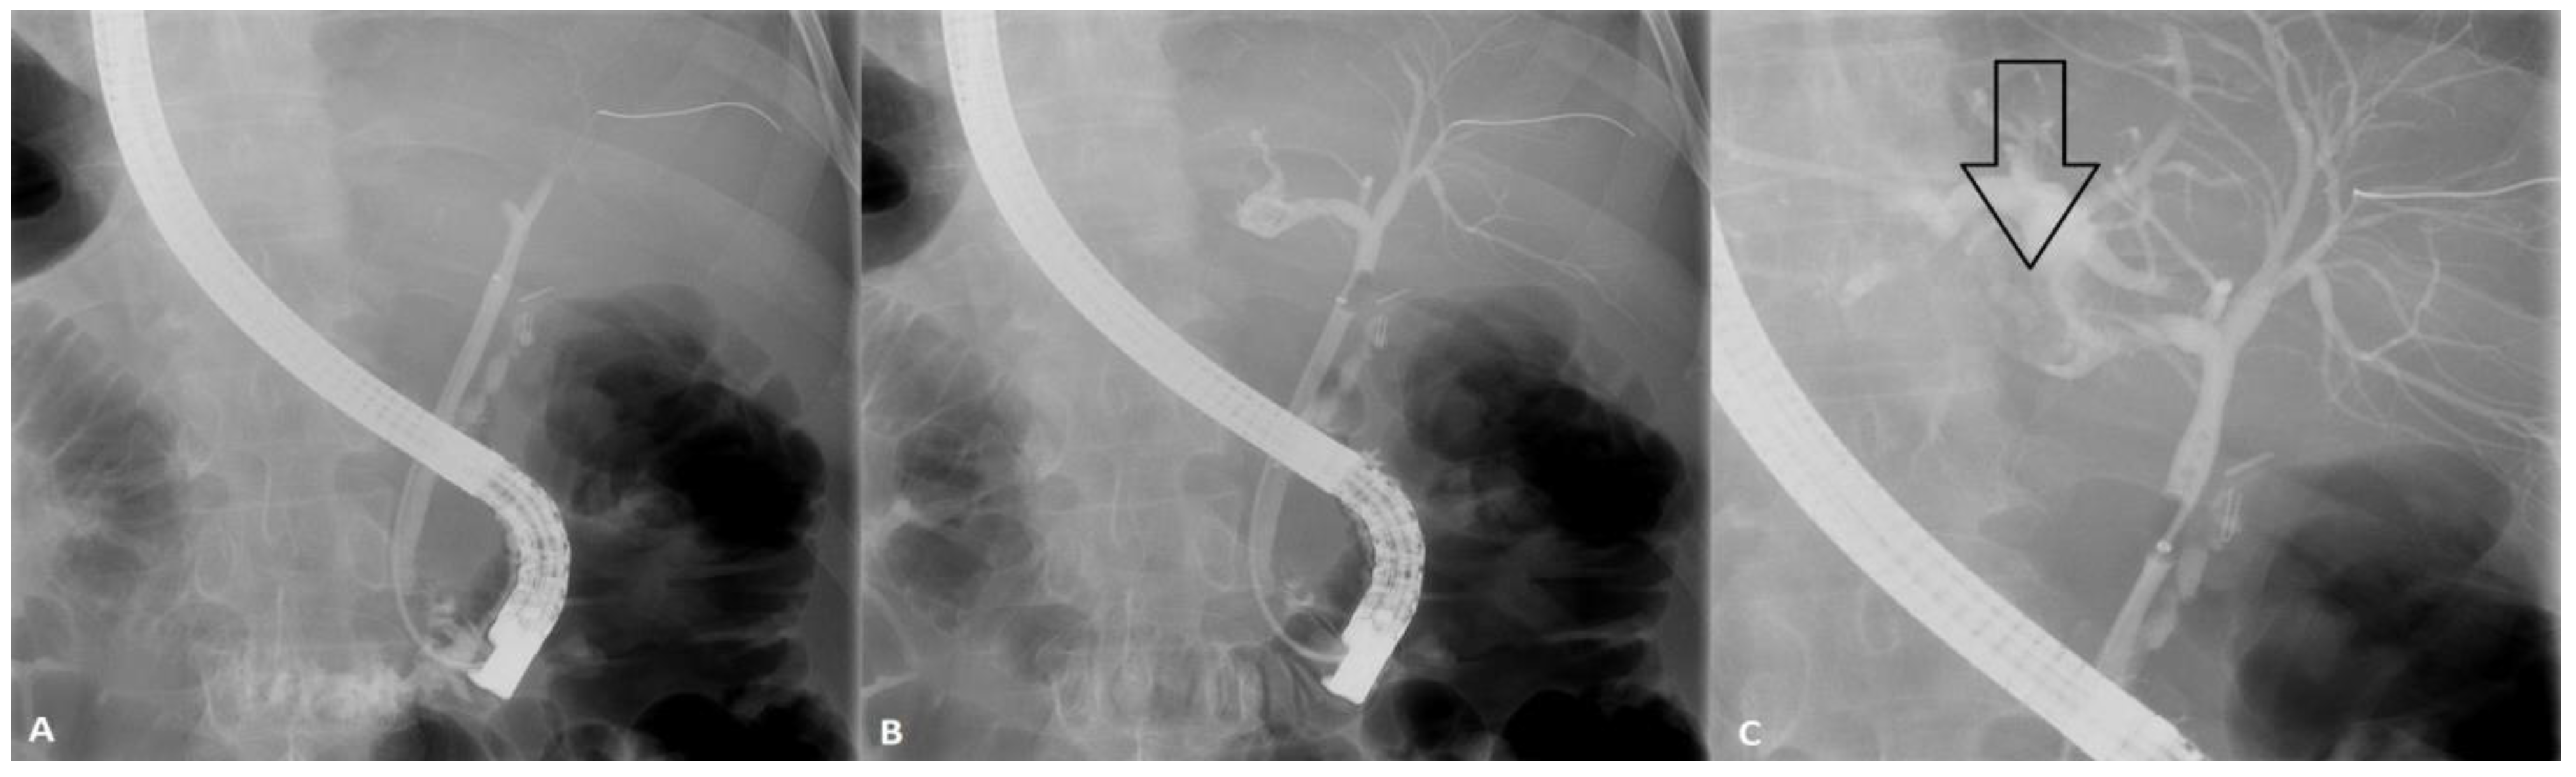

A guidewire was directed towards this anomaly and due to its twisted and narrow connection to the CBD, the decision was made to place a naso-biliary drainage tube (NBDT). Over the next 7 days the drainage was used to pour saline into the intrahepatic biliary abnormal dilation, at a rate of circa 1000-1500 ml per day.

Figure 2. Naso-biliary drainage placement into the biliary lake (A), efficient downstream drainage (B) and clearance of the biliary stone conglomerate (C).

Radiology studies showed by this time significant reduction in the biliary stone conglomerate, so ERCP was attempted two days later and the NBDT was extracted with insertion of 3 biliary plastic stents of 7 French each with their proximal part inside the biliary lake.